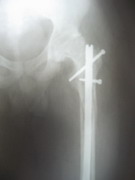

TRAUMA

Besides routine trauma, we specialize in advanced traumatology. We manage all the pelvic and acetabular fractures and spinal fractures with neurological deficit, with equal case.